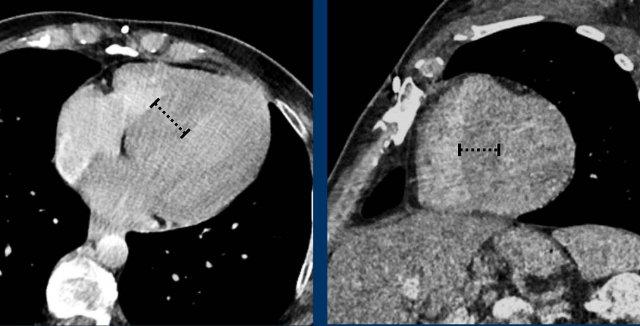

Hình ảnh

Phì đại tâm thất trái đồng tâm trong tăng huyết áp mạn tính với độ dày lên đến 26 mm tại vách liên thất đoạn nền.

Đây là bất thường ngay cả trong thì tâm thu.